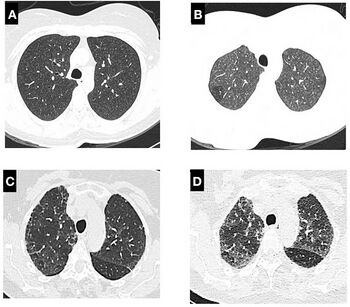

A chest X-ray or CT is necessary to differentiate between pneumonitis and pneumonia of an infectious etiology. Some degree of pulmonary fibrosis may be evident in a CT which is indicative of chronic pulmonary inflammatory processes. Diagnosis of Pneumonitis is often difficult as it depends on a high degree of clinical suspicion when evaluating a patient with a recent onset of a possible interstitial lung disease. In addition, interpreting pathologic and radiographic test results remains a challenge to clinicians. Pneumonitis is often difficult to recognize and discern from other interstitial lung diseases.[7]

Clinical tests include chest radiography or (HRCT) which may show centrilobular nodular and ground-glass opacities with air-trapping in the middle and upper lobes of the lungs. Fibrosis may also be evident. Bronchoalveolar Lavage (BAL) findings coinciding with pneumonitis typically include a lymphocytosis with a low CD4:CD8 ratio.[7][12]

Reticular or linear patterns may be observed in diagnostic imaging.[7] Pneumonitis may cause subpleural honeycombing, changing the shape of the air spaces in an image, which may be used to identify the respiratory disease.[7] The interlobular septa may also thicken and indicate pneumonitis when viewed on a scan.[7]

Since pneumonitis manifests in all areas of the lungs, imaging such as chest x-rays and Computerized tomography (CT) scans are useful diagnostic tools.[3] While pneumonia is a localized infection, pneumonitis is widespread.[3] A spirometer may also be used to measure pulmonary function.